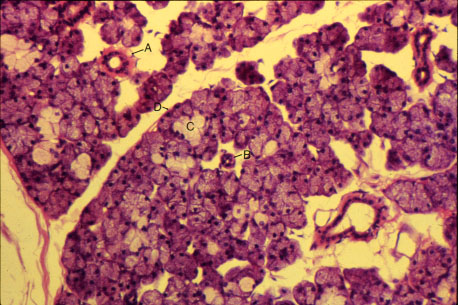

K-slide 62: Still higher magnification of slide 60

A. Striated duct

B. Intercalated duct

C. Mucous tubule

D. Serous demilune

Note that most secretory units are serous acini.